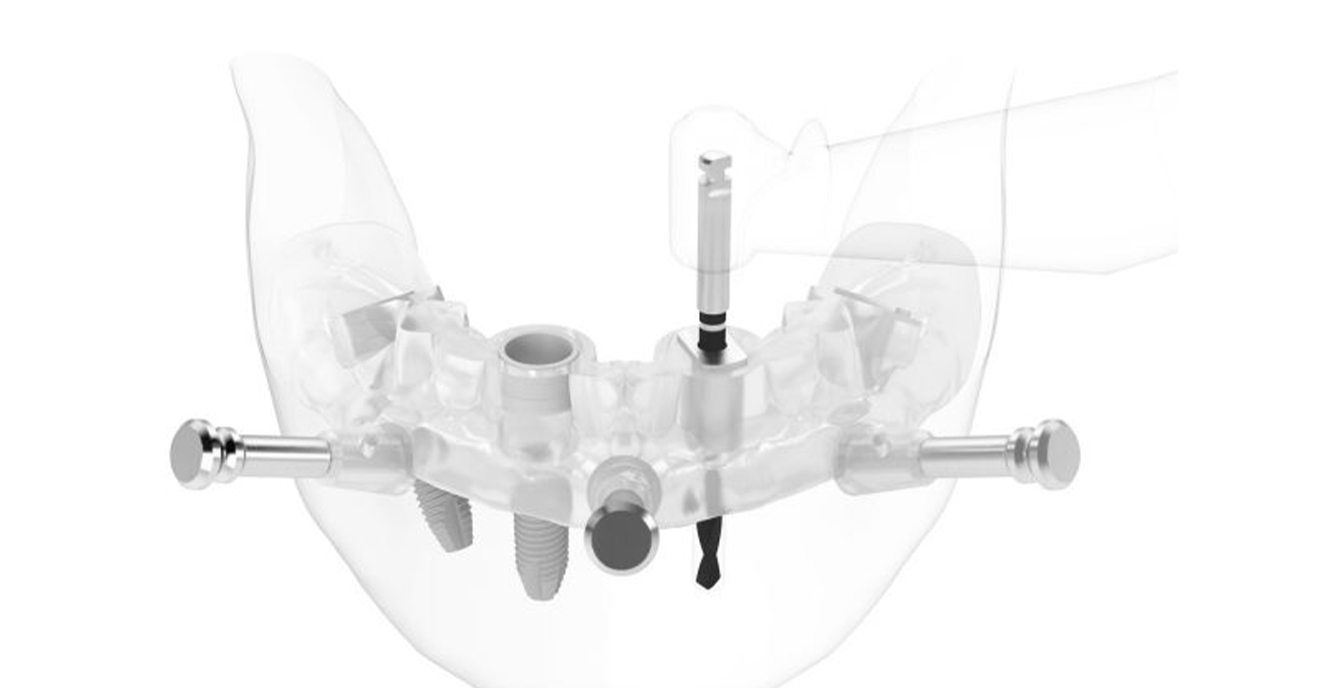

「ノーベルガイド」は、歯肉を切開せずにインプラントを埋入するノーベル独自のガイドシステムです。術前のデジタルシミュレーションとガイドテンプレートで正確な埋入と低侵襲な手術を実現し、患者様のご負担を軽減します。